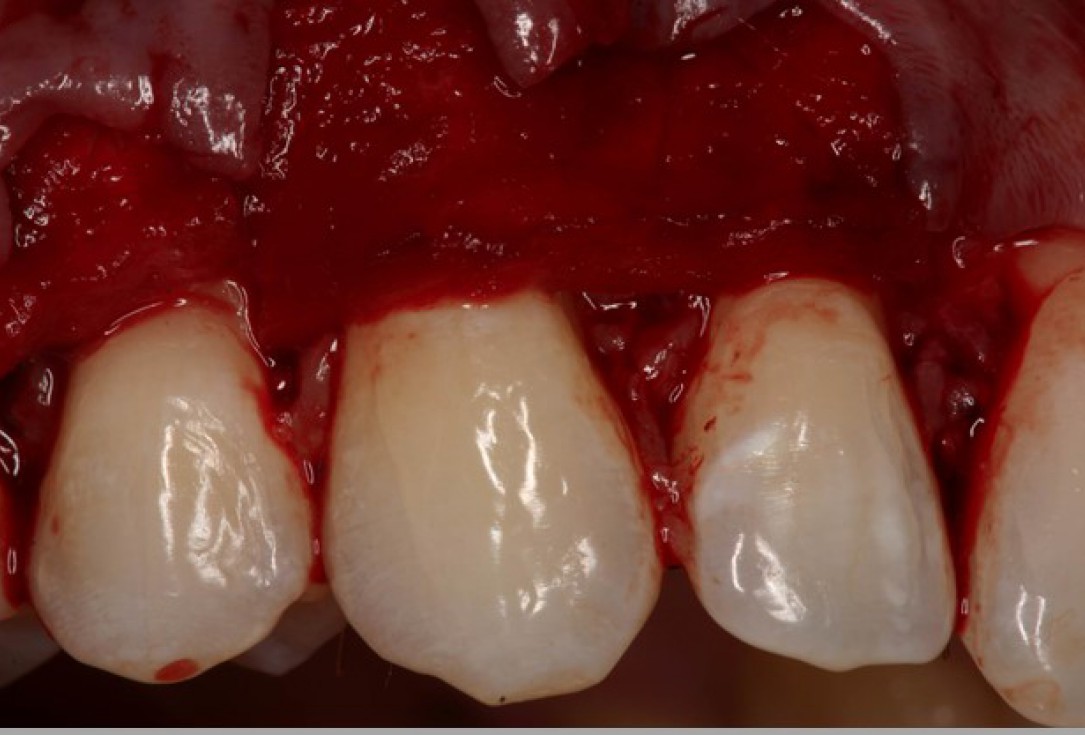

02/06 - Flap preparation according to the modified coronally advanced flap technique (Zucchelli & De Sanctis J Periodontol. 2000). Sulcular incision from tooth 11 to 15 and elevation of a splitthickness flap.Multiple gingival recessions treated with the modified coronally advanced flap in conjunction with mucoderm® - Prof. Dr. Dr. A. Kasaj